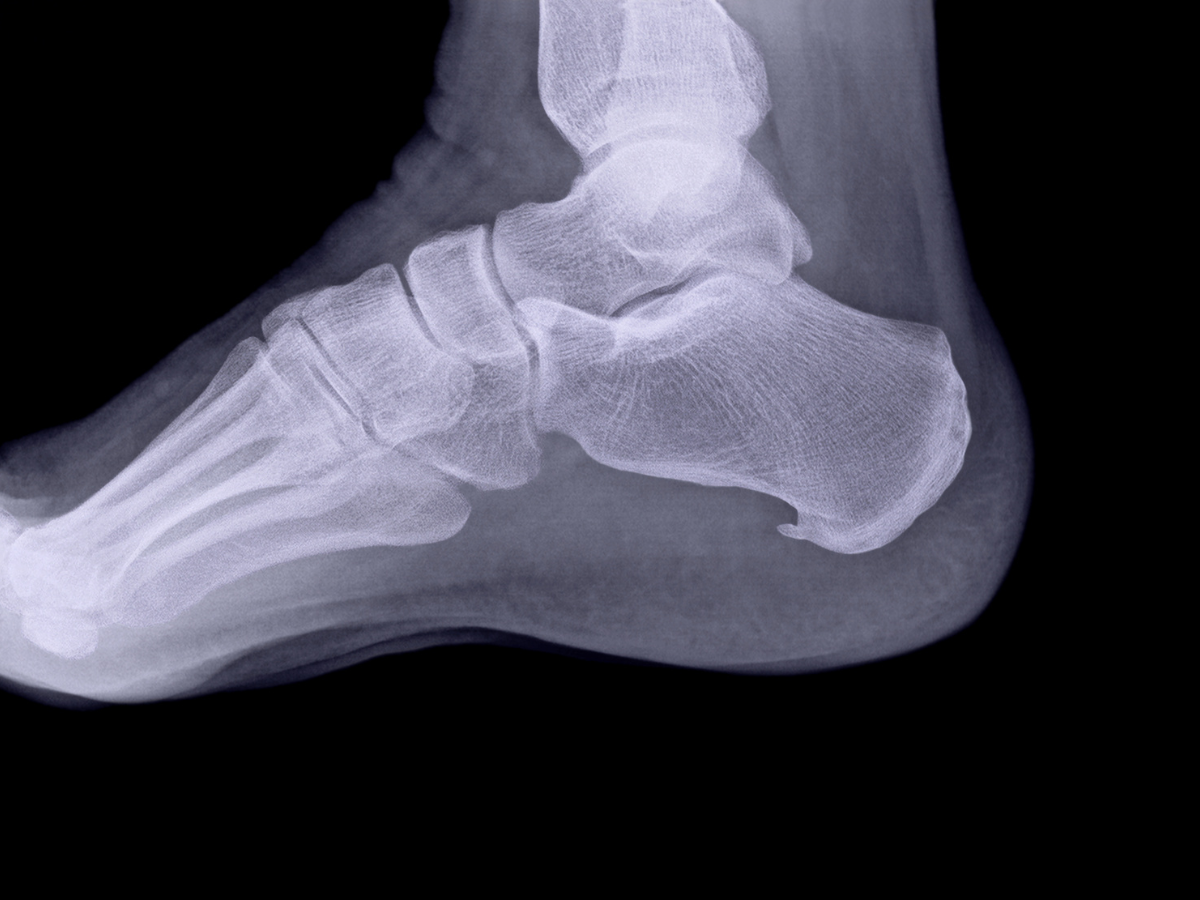

- Use supportive footwear and avoid excessive joint strain, especially for those with very active lifestyles.